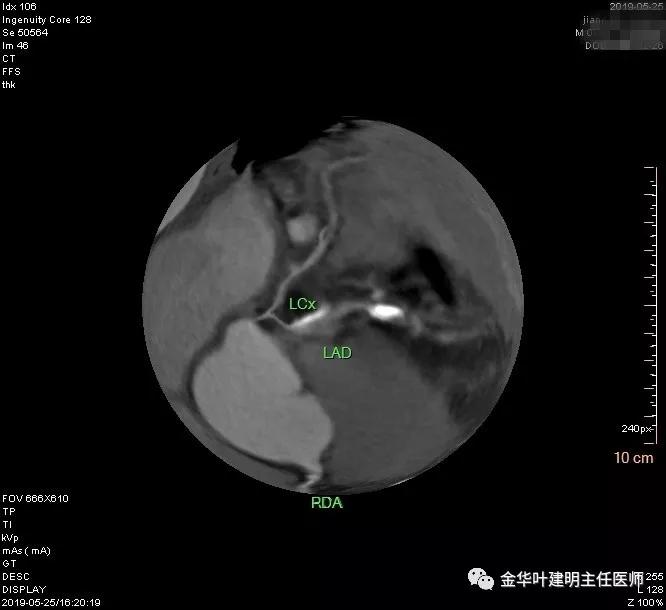

术前检查冠脉CT示:左冠前降支近段多发钙化斑块伴管腔重度狭窄(约85%),建议DSA检查。但追问病史以往平时无胸痛或胸闷症状,运动试验提示可疑阳性(上斜型压低),活动后胸闷气闭症状不明显,既往否认高血压、糖尿病。所以经过心内科会诊讨论,认为还是可以进行手术。术前冠状动脉CT示: